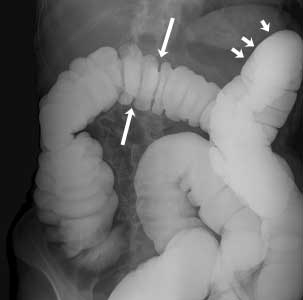

Colon normal

Cortesía de Intermountain Medical Imaging, Boise, Idaho. Todos los derechos reservados.

Esta imagen muestra un colon normal lleno de bario. El bario se ve blanco en la imagen. Las flechas indican las curvas normales del colon.